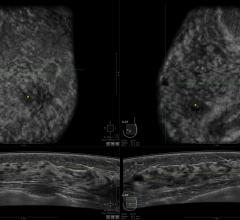

Angiography, Computed Tomography (CT), Flat Panel Displays, Information Technology, Magnetic Resonance Imaging (MRI), Mobile C-Arms, Nuclear Imaging, Ultrasound Imaging

Canon Medical Systems’ offering includes: computed tomography, magnetic resonance, ultrasound, X-ray, cath and EP lab